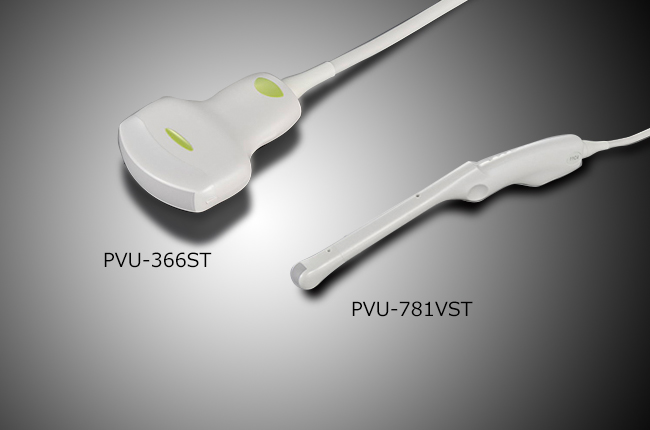

Підтримка широкої лінійки широкополосних мультифокальних датчиків з частотою до 14 MHz.